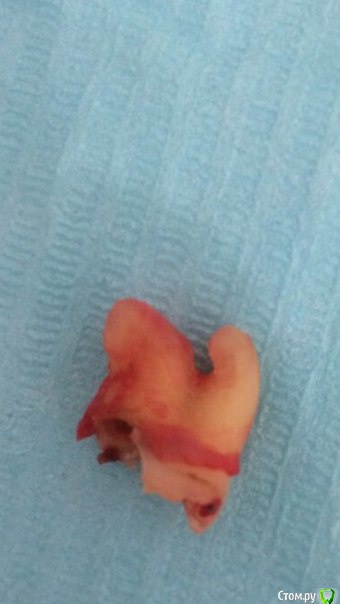

dantist_movani Опубликовано 9 октября, 2015 Поделиться Опубликовано 9 октября, 2015 (изменено) дистопированная резорцинка - пришлось изничтожить по кусочкам удаляйте фото из цитатзлая осьминожка) Долго удаляли? Изменено 9 октября, 2015 пользователем IvanK 2 Ссылка на комментарий